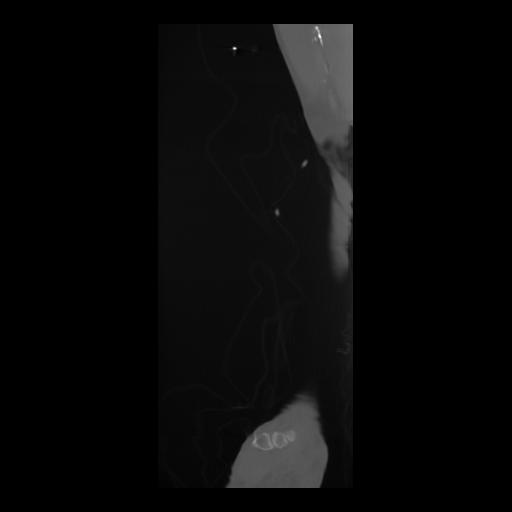

36 CUERPO,CE,Sagittal,3.000,CUERPO,Sagittal,